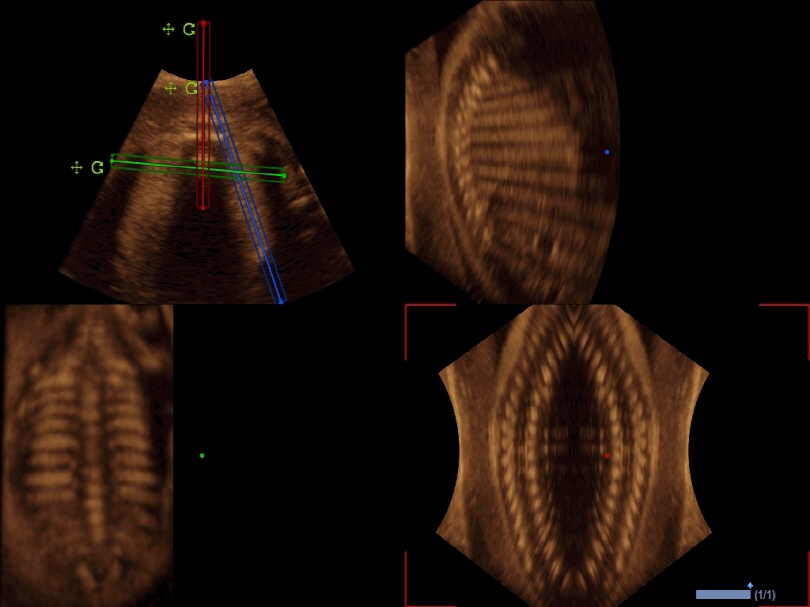

VC1-6T

Volume Convex (1-6MHz)

Application:

Abdomen, OB, GYN, EM

VE3-10H

High density volume endocavity transducer (3-10MHz)

Application:

GYN, OB, Urology, EM